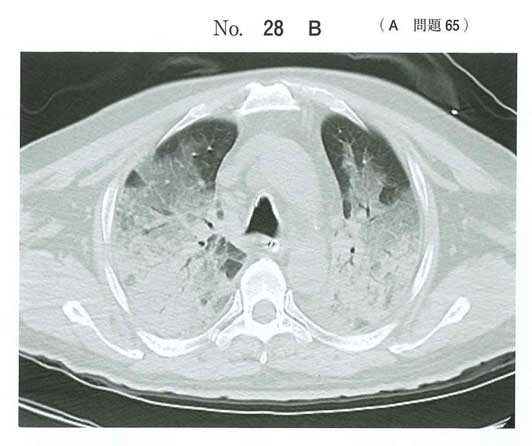

ARDSの問題とはこれですか。

ARDSというよりただの溺水では

海水溺水は浸透圧差から肺水腫をきたしやすいとされています